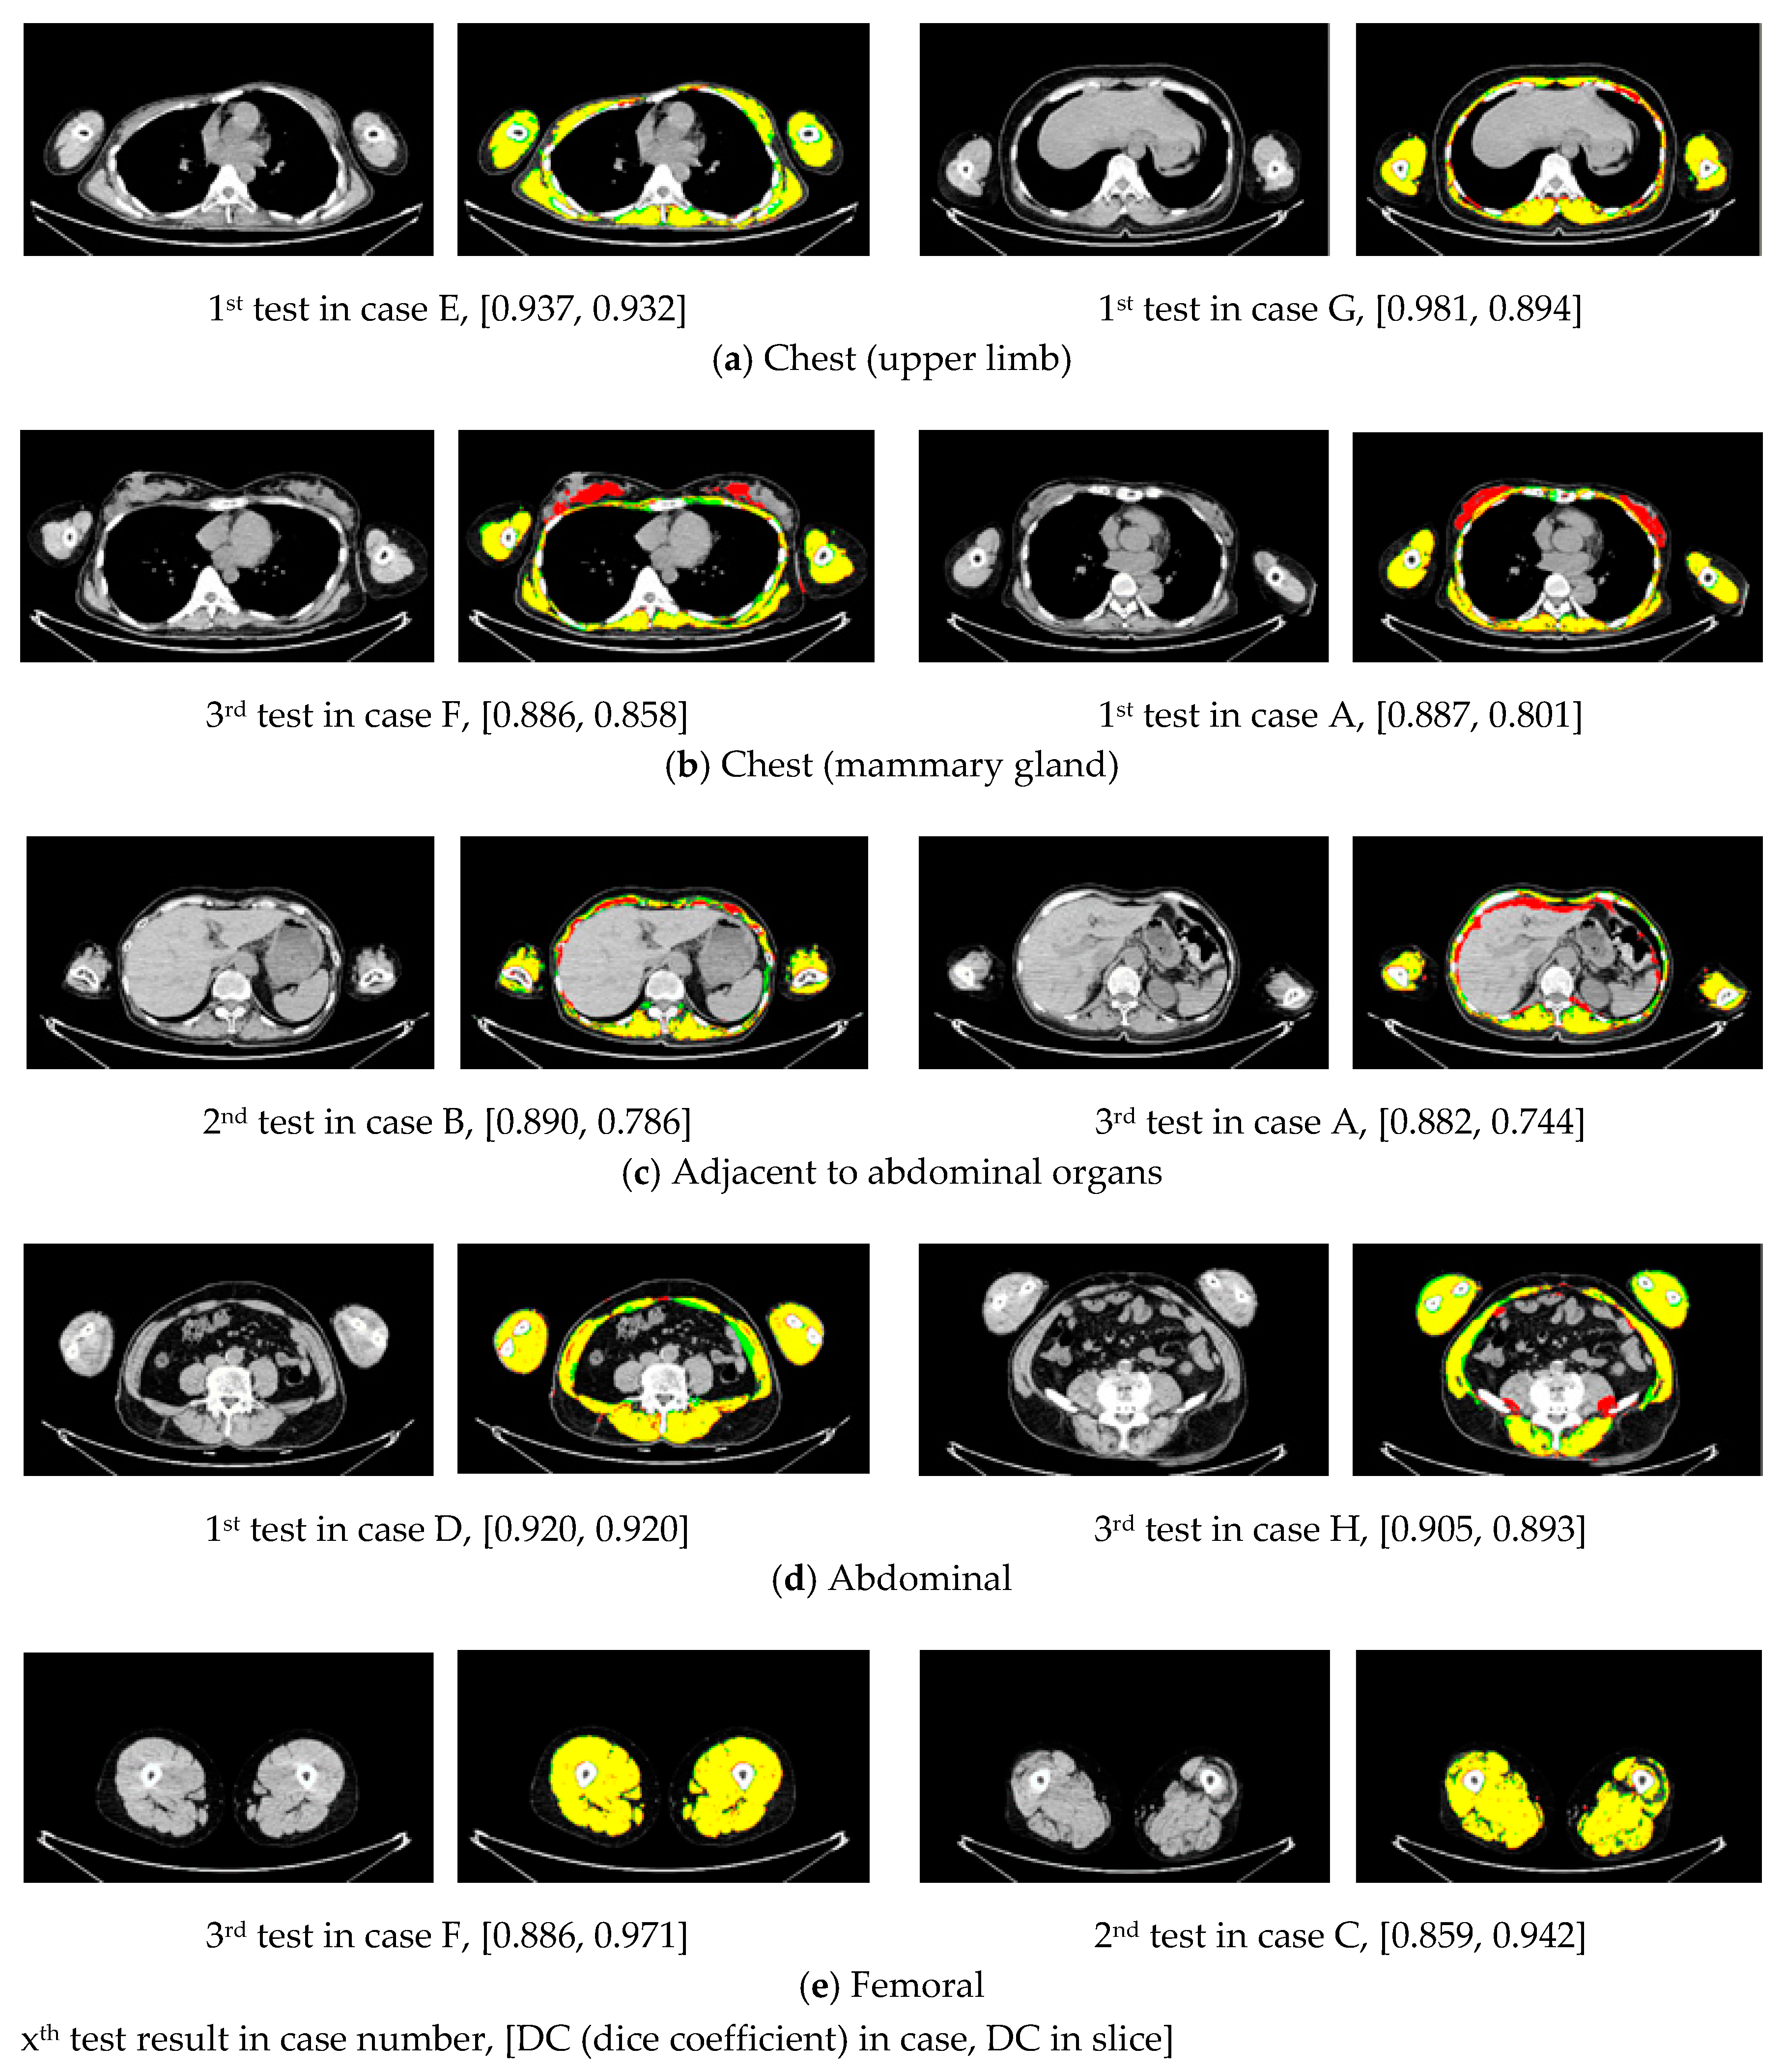

Figure 4.

Slice example of the segmentation results in each section [DC (dice coefficient) in case, DC in slice]. The left column is a good result and the right column is a bad result. Yellow, red, and green show the overlapped area between ground truth and the result, the over-extracted, and unextracted regions, respectively. In (a,e), the segmentation results were accurate for areas not adjacent to the limbs and abdominal organs. Over-extraction occurred in the mammary gland area (b) and the area where the surface muscle was adjacent to the abdominal organ (c). Un-extraction occurred in the surface muscles of the abdomen where the recognition target was small (d). DC, dice coefficient.

Table 1 shows the DC of three experiments in eight test cases. The mean DC was 0.900 (SD: 0.022) for surface muscle segmentation. Here, SD is obtained from the DC values of all experimental results, and the results obtained for each of the three tests. The segmentation results of Case E (Figure 3) obtained the highest DC (0.937) in the first experiment and comparison with our 2D U-Net based approach [13]. Figure 4 shows an example of the characteristic segmentation results of the surface muscles in each section. Blood vessels were over-extracted in the surface muscles of the limbs and areas not adjacent to the organs, but no major mis-extraction was observed in other tissues, and the segmentation was successful. On the other hand, over-extraction of the mammary gland region and the abdominal organs adjacent to the surface muscles and unextracted in a small region of the rectus abdominis and oblique muscles were observed. Despite those remaining issues, the conventional 2D U-Net for surface muscle segmentation [13] has a DC of 0.749, whereas the proposed method had a higher DC value (0.900).

There are some limitations to our study. First, the number of images when creating a VP was fixed at 56. For the creation of the VP, we selected 56 because it was the maximum number of slices that could be learned by the GPU in this experimental environment. Thus, we did not consider another number of slices. Therefore, for the segmentation of the surface muscles using VP, determination of the number of slices composing the VP remains to be studied. However, it is necessary to consider that changing the number of slices requires the creation of new ground truth labels. In this study, surface muscles were defined as skeletal muscles outside of the body cavity, and whole-body CT images taken with a standard protocol were used. The training increases as the number of slices increases, so improving the DC rate is possible. However, ground truth segmentation of skeletal muscle on non-contrast CT is not easy. It is difficult to increase the ground truth easily because it is hard to strictly distinguish tissues such as microvessels and tendons. On the other hand, if the training VP is composed of less than 56 slices, the number of features that can be extracted and the segmentation result will decrease accordingly. However, by reducing the number of images that make up the training VP, there is an advantage of a reduced cost of creating ground truth labels, and the number of learning cases can be increased. It is necessary to examine the change of the segmentation result and determine the number of slices constituting the training VP required for the surface muscle segmentation when taken all together. Furthermore, even when selecting the same 56 slices, a different slice selection method, based on the anatomical position in each case, could be considered (instead of selecting equal intervals). The reason is that slices required for training are not included in the VP slice from the high-density mammary gland in the over-extracted region or abdominal region that were not extracted (Figure 4). Therefore, it is necessary to consider the slice selection method that constitutes the training VP. However, when selecting slices based on the anatomical position, the variation of the surface muscles in each training VP is reduced, so the generalization performance for surface muscle segmentation in regions other than the selected slice may decrease. Therefore, it is necessary to consider the enhancement of training by augmentation.